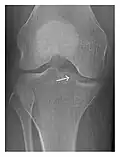

Figure 1: A 56-year-old woman presenting with left knee pain after a fall. (a) Initial anteroposterior radiograph was considered normal, however, subtle cortical disruption of the anterior rim of the medial tibial plateau, medial to the tibial spine, is noted (arrow). (b) Coronal T1-weighted MRI confirms the cortical disruption (arrow) and shows extensive fracture through the proximal tibia. (c) Coronal proton density-weighted image with fat saturation shows extensive edema in the subchondral bone. Note also hypersignal adjacent to the medial collateral ligament corresponding to a grade I sprain (arrowheads).[1]